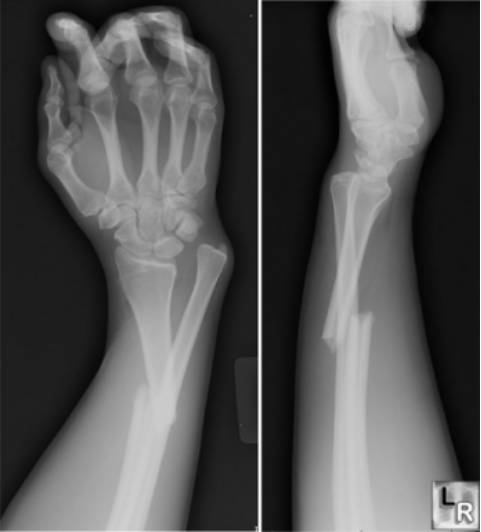

Colles骨折

桡骨远端伸直型骨折,远折端向桡背侧移位。是关节外骨折,常伴有尺骨茎突骨折。

Smith骨折

桡骨远端屈曲型骨折,骨折远端向掌桡侧移位。